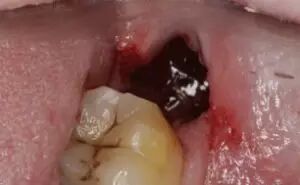

目前认为干槽症是智齿拔除术后发生在拔牙窝局部的局限性骨炎。正常的拔牙窝愈合是牙齿拔出术后,血块充满拔牙窝后形成了高质量的充填物,凝固后保护拔牙窝,促进伤口的愈合。而在愈合过程中,如果凝血块脱落或者感染,就可能会导致干槽症。

正常拔牙窝会有血凝块保护